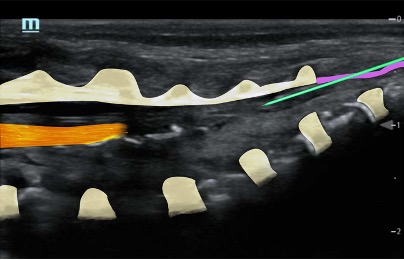

- At birth, the ossification centres of the spine are at an early stage of development; it is therefore possible to obtain excellent spinal images in neonates. With age and increasing ossification, the US window to the spine diminishes (the ossification is complete at 21 years old)

Caudal in a neonate

Caudal in a two year old

Mapping/scout scan: look between the intervertebral spinous processes and laminae:

1)Probe position transverse over the sacral cornua (-> frog’s eyes US view)

2)Then rotate probe 90 degrees for a longitudinal view

Identify:

•Sacral cornua

•Sacrum

•Sacrococcygeal membrane

•End of the dural sac (hyperechoic (<-> CSF are anechoic (black)

•Caudal epidural space

•Assess the position of the dural sac in relation to the sacrococcygeal membrane

NOTE: Ultrasound can't see through bone; so with increasing age (= increasing angulation of the spinous processes and increasing ossification of the laminae) the size of the echo window will diminish -> you might need to scan paramedian

TIP: use a large linear probe (50mm) – this will allow you to visualise more vertebrae in one image for easier monitoring of needle approach and LA spread